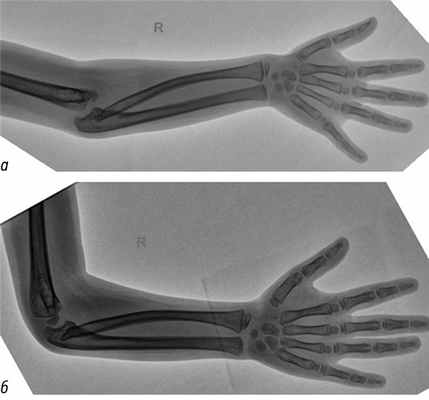

5. Рис. 5. Функциональная рентгенография с попыткой выведения правого предплечья в стандартное положение: а — задний вывих костей предплечья в положении разгибания; б — в положении сгибания вывих устранен